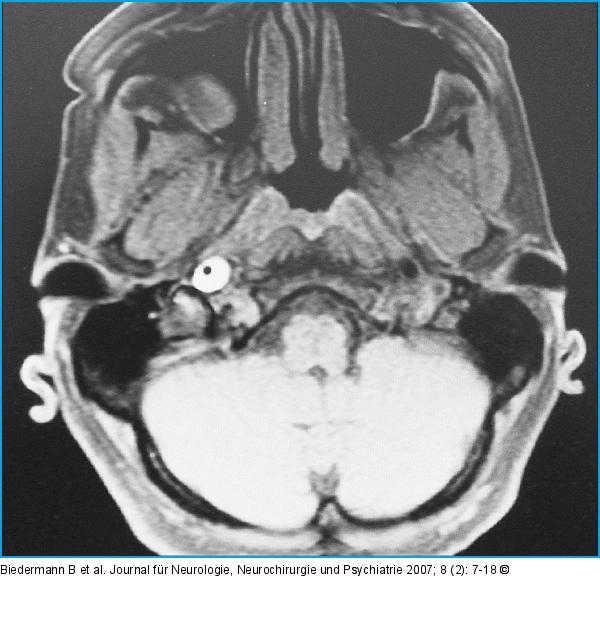

Abbildung 2: Horner-Syndrom Zerebrales MRT in fettgesättigter T2-Gewichtung: Darstellung des halbmondförmigen Wandhämatoms der ACI rechts knapp oberhalb der Bifurkation bis in die Pars petrosa reichend bei einem 50jährigen Patienten (siehe Abb. 1), der nur mit einem Horner-Syndrom und Kopfschmerzen symptomatisch wurde (mit freundlicher Genehmigung von Dr. T. Gotwald, Radiologie II, Medizinische Universität Innsbruck) |

Abbildung 2: Horner-Syndrom

Zerebrales MRT in fettgesättigter T2-Gewichtung: Darstellung des halbmondförmigen Wandhämatoms der ACI rechts knapp oberhalb der Bifurkation bis in die Pars petrosa reichend bei einem 50jährigen Patienten (siehe Abb. 1), der nur mit einem Horner-Syndrom und Kopfschmerzen symptomatisch wurde (mit freundlicher Genehmigung von Dr. T. Gotwald, Radiologie II, Medizinische Universität Innsbruck) |